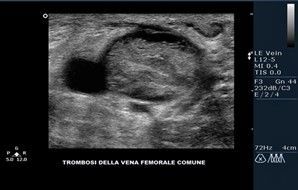

Ecocolordoppler venoso

È possibile seguire l’asse venoso, superficiale o profondo, localizzare e quantizzare l’estensione del reflusso lungo tutto il suo decorso cranio-caudale.

- presenza di ostruzioni (trombi)